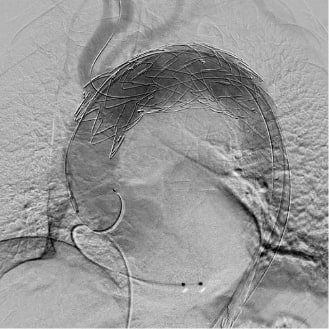

ステントグラフト挿入後